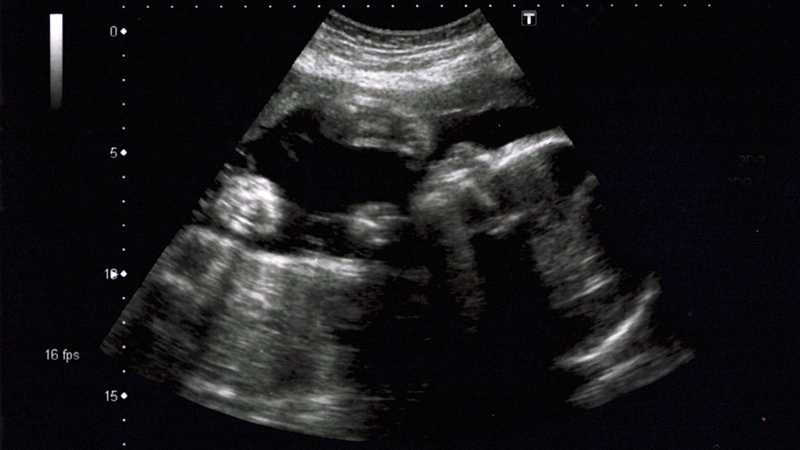

NICU Scene Week 26 ultrasound scan